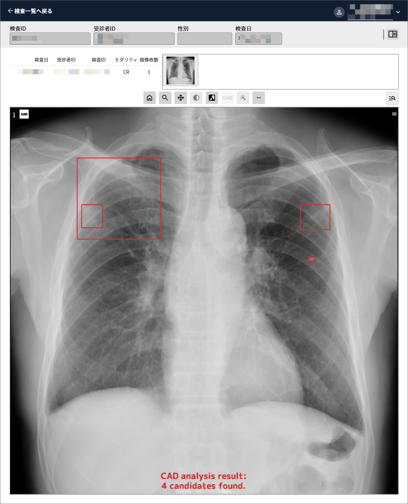

. 胸部X線画像読影支援

医用画像解析ソフトウェア EIRL Chest XR ※胸部X線画像から条件を満たす対象領域を検出し、医師による読影をサポートします

本ソフトウェアを用いて読影した場合、専門医で 11.1 %、経験 5 年未満の非専門医で 15.5 %の感度が上がることが認められました

また、読影試験における診断性能を表す JAFROC 解析によるFOM ( Figure Of Merit ) 値は、本品を併用すると専門医で 0.059 ポイント 向上し ( p < 0.001 ) 、読影精度の向上が認められました *

* 異常陰影が認められる有所見画像 88 症例及び正常画像 266 症例の胸部単純X線画像を対象とした、10 名の医師による読影試験の結果※診断を意図した機能ではありません

販売名:医用画像解析ソフトウェア EIRL Chest XR 医療機器承認番号:30400BZX00285000 製造販売業社:エルピクセル株式会社